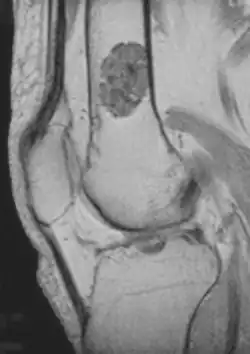

Diagnosis is by X-ray, CT scan and sometimes MRI.[4] Most occur as a less than three centimetre size single tumor. When several occur in one long bone or several bones, the syndrome is called enchondromatosis.[4]

- magnetic resonance imaging (MRI)[7] – a diagnostic procedure that uses a combination of large magnets, radiofrequencies, and a computer to produce detailed images of organs and structures within the body. This test is done to rule out any associated abnormalities of the spinal cord and nerves.